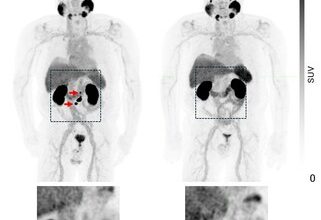

Cision PR Newswire23 February 2026SECuRE trial update: Another participant with undetectable PSA & negative PSMA PET

HIGHLIGHTS Another participant with metastatic castration-resistant prostate cancer (mCRPC) in the Cohort Expansion Phase (Phase II; 8 GBq of 67Cu-SAR-bisPSMA…